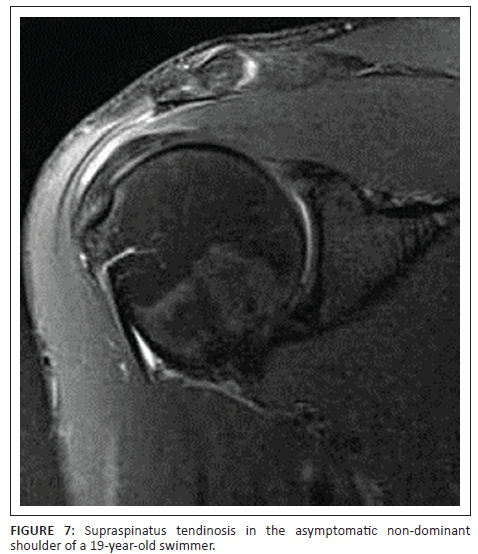

Of the 29 asymptomatic shoulders studied, 25 (86.2%) had MRI changes which could be viewed as abnormal. Ten (91%) of the 11 symptomatic shoulders had abnormal MRI findings. The most common MRI findings (Figures 1-3) in the symptomatic shoulders were supraspinatus partial tear (45.5% in symptomatic shoulders vs. 20.7% in asymptomatic shoulders), subacromial subdeltoid fluid (45.5% vs. 34.5%), increased signal in the AC Joint (45.5% vs. 37.9%), supraspinatus tendinosis (36.4% vs. 10.3%) and AC joint arthrosis (36.4% vs. 34.5%). Supraspinatus tendinosis (36.4% vs. 10.3%) and partial tear of the supraspinatus (45.5% vs. 20.7%) were much more common in the symptomatic shoulders compared with the asymptomatic shoulders. Biceps tendinosis was common in both symptomatic and asymptomatic shoulders (18.2% vs. 6.9%). Degeneration in the proximal bicipital groove (18.2% vs. 0%) was more common in the symptomatic population. Thickening of the inferior glenohumeral ligament was more common in the asymptomatic shoulders (13.8% vs. 0.0%). Increased signal of the labrum and labral tears were comparable in the two groups (10.0% vs. 10.3%).

Of the asymptomatic shoulders studied, 86.2% had MRI changes which could be viewed as abnormal. This corresponds to previous studies that showed that MRI abnormalities in asymptomatic overhead athletes are common.2,4,11 The most common findings in both the symptomatic and asymptomatic shoulders were subacromial subdeltoid fluid (Figure 5), increased signal at the AC joint (Figure 6), AC joint arthrosis, supraspinatus tendinosis (Figure 7) and biceps tendinosis (Figure 8). There were 11 symptomatic shoulders in our sample group with the most common clinical findings being impingement, AC joint tenderness, positive O' Brien's sign and biceps tenderness. The asymptomatic group also demonstrated positive clinical findings, with subacromial impingement, biceps tenderness and sternoclavicular tenderness being the most common findings. AC Joint tenderness was less common in the asymptomatic group. The studied group consisted of a slightly smaller symptomatic group than Sein et al., but our athletes more frequently demonstrated local AC joint tenderness and positive O'Brien's sign. Increased signal at the AC joint is a common finding in both the symptomatic and asymptomatic shoulders of overhead athletes and does not correlate with patient symptomatology as also noted in agreement with Reuter et al.12 In this study, type 1 acromion shape was most common followed by type 2 and type 3. There was no direct correlation between shoulder pain and acromion shape.

Supraspinatus tendinopathy was a common finding in both the symptomatic and asymptomatic shoulders, with it being nearly twice as common in the symptomatic shoulders. Previous studies also found supraspinatus tendinopathy to be a dominant finding.4 Biceps tendinosis was approximately twice as common in the symptomatic shoulder. Connor et al. showed that subacromial subdeltoid fluid was a common finding in the asymptomatic shoulder.6 This study demonstrated similar results with subacromial and/or subdeltoid fluid found in 34.5% of the asymptomatic shoulders. In a study where Reuter et al. evaluated shoulder MRI changes in 23 triathletes, 57% of the asymptomatic group and 31% of the symptomatic group demonstrated AC joint arthrosis.12 The current study demonstrated nearly equal percentages of AC joint arthrosis (36.4% symptomatic vs. 34.5% asymptomatic).